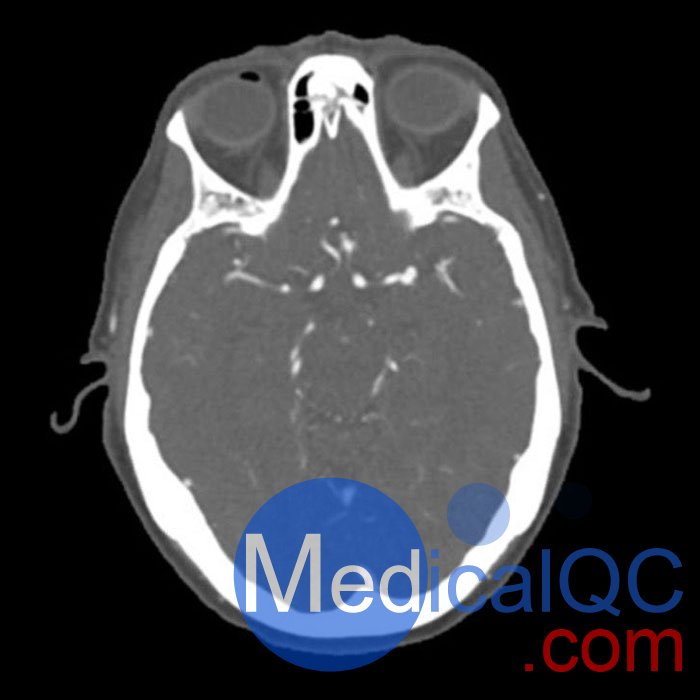

CTA是通過靜脈注射對比劑,以全身血管為檢查對象,利用CT設(shè)備進(jìn)行血管成像,是目前臨床上診斷心腦血管及外周血管疾病常用的無創(chuàng)性檢查方法。

WEK50-03動脈瘤頭模,WEK50-03血管造影CTA頭模是頭部 CTA 動脈瘤模型

模擬造影劑動脈期頭部增強(qiáng)(CT血管造影)。 它覆蓋了頂點(diǎn)枕骨大孔。

該體??捎糜贑T(包括CBCT)評估和優(yōu)化成像性能和人工智能診斷。 這是也適合培訓(xùn)目的。

模型提供了詳細(xì)且真實(shí)的模擬常見的大腦病理,軟和骨組織。 空氣空隙充滿了約的纖維素聚合物復(fù)合材料 -160HU。

WEK50-03動脈瘤頭模,WEK50-03血管造影CTA頭模影像圖:

更多效果和DICOM數(shù)據(jù)請聯(lián)系我們